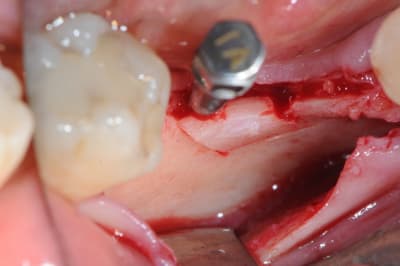

Cas 1-coté gauche maintenant:

photo:

1- ouverture, forme et configuration différente

2- une fois échauffée avec le coté droit, je me dis allez hop, j'attaque une expansion. donc incision crestale avec décharges osseuses

3- mise en place des expanseurs de Mesinger A et B

4-5 notez que l'incision de décharge étant oblique , elle sert également de garde fou contre une éventuelle fracture osseuse. l'os "mobile" vient buter contre l'os "immobile"

la suite en primeur pour ceux qui viennent à Sallanches les 28 et 29 Mars...